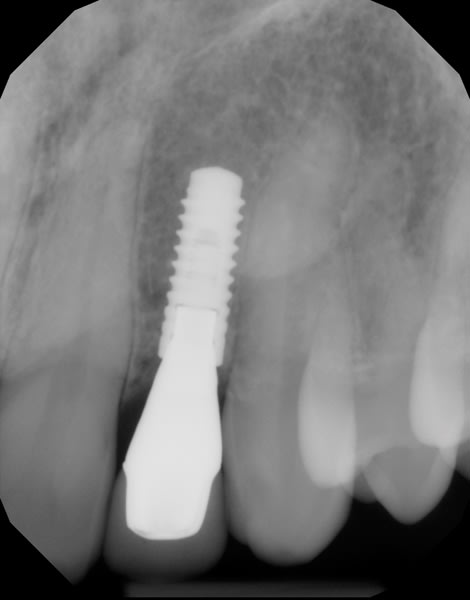

Both provisional restorations were removed, the definitive abutments were connected, and the abutment screws were torqued to 35 Ncm. The accuracy of the abutment margins at the gingival level, as transferred from the original custom scan body, is demonstrated in Figure 24. A cotton pellet and elastic, single-component, light-cured resin was placed to close the abutment access hole and light cured. The definitive restorations were cemented with radiopaque glass ionomer luting cement (Figure 25 through Figure 29).